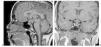

Casos en imagen 4

Case 4

Figuras (3)